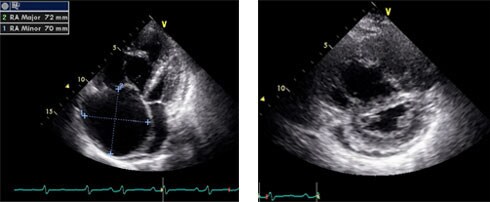

Echocardiogram